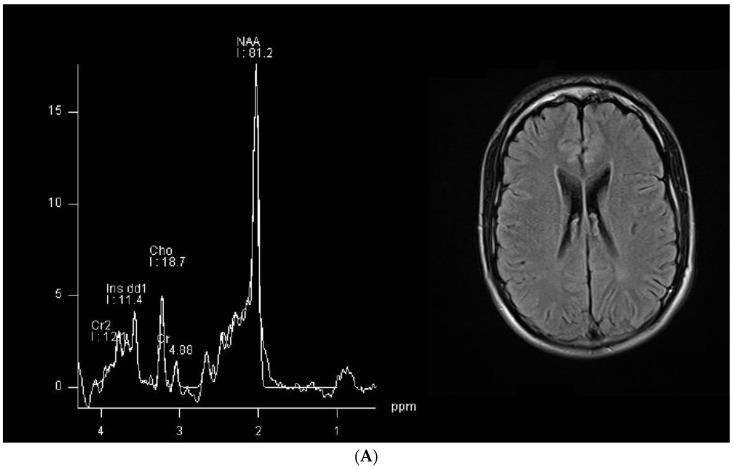

(1) Background: In hereditary creatine transporter deficiency (CTD), there is an absence of creatine in the brain and neurological symptoms are present, including severe language impairment. However, the pathological changes caused by creatine deficiency that generate neuropsychological symptoms have been poorly studied. (2) Aims: To investigate if the language impairment in CTD is underpinned by possible pathological changes. (3) Methods: We used MRI tractography to investigate the trophism of the left arcuate fasciculus, a white matter bundle connecting Wernicke's and Broca's language areas that is specifically relevant for language establishment and maintenance, in two patients (28 and 18 y.o.). (4) Results: The T1 and T2 MRI imaging results were unremarkable, but the left arcuate fasciculus showed a marked decrease in mean fractional anisotropy (FA) compared to healthy controls. In contrast, the FA values in the corticospinal tract were similar to those of healthy controls. Although white matter atrophy has been reported in CTD, this is the first report to show a selective abnormality of the language-relevant arcuate fasciculus, suggesting a possible region-specific impact of creatine deficiency.

https://cdn.ncbi.nlm.nih.gov/pmc/blobs/9a95/11048612/e0a66fe8e7b9/brainsci-14-00337-g001a.jpg